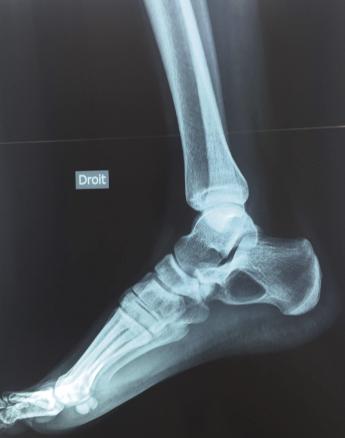

La radiographie et l’échographie du pied droit montrent une discrète inflammation du ligament calcanéo-fibulaire et une importante lésion lacunaire du calcanéum (fig. 1).